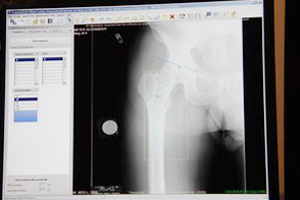

整形外科領域においては,例えば一般撮影を用いて股関節の人工関節を計測する際に,ワンクリックで簡単に正確に行えるシミュレーションツールが搭載された。

Centricity IW(整形領域)